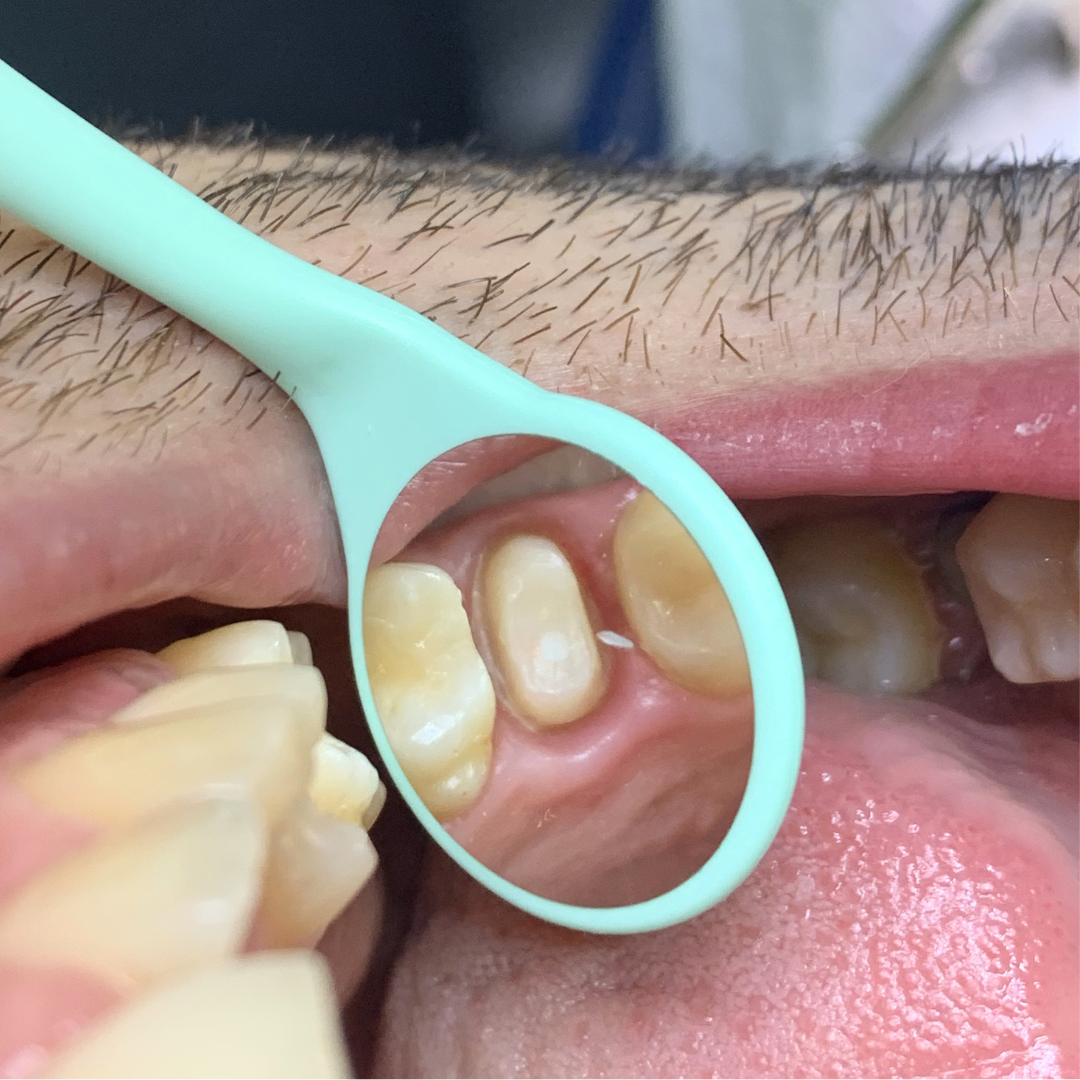

Pacienta s-a prezentat cu o fractura coronara la nivelul incisivului lateral.

Aspectul radiologic dupa tratamentul de canal, inserarea pivotului si cimentarea coroanei definitive.